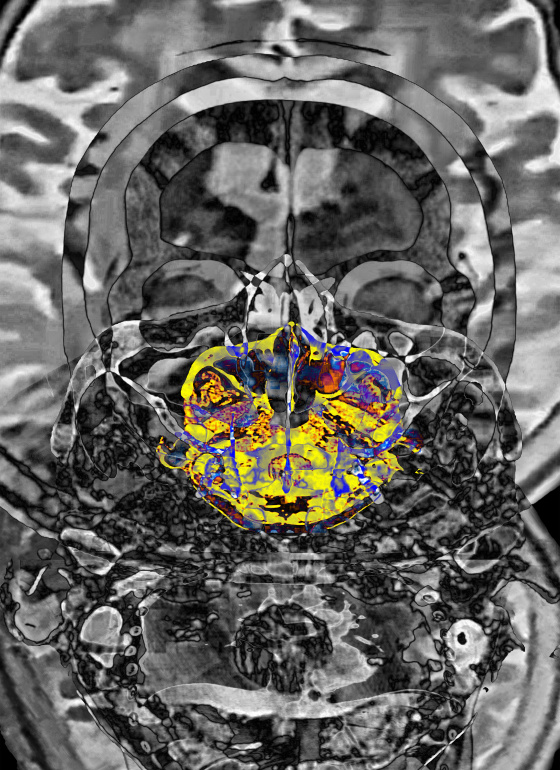

Stroke is due to partial blood circulation disturbance in the brain, resulting in partial loss of body function. When the right hemisphere of the brain is stroke, there will be left side defects. On the contrary, left hemisphere stroke is right paralysis or partial paralysis. This work is mainly designed based on the brain images of CT scan and MRI, emphasizing the thinking space of the brain and controlling people's behavior patterns. In this spatial structure, the pathological manifestations of translational medicine are integrated into the left and right inverted images in philosophical thinking.